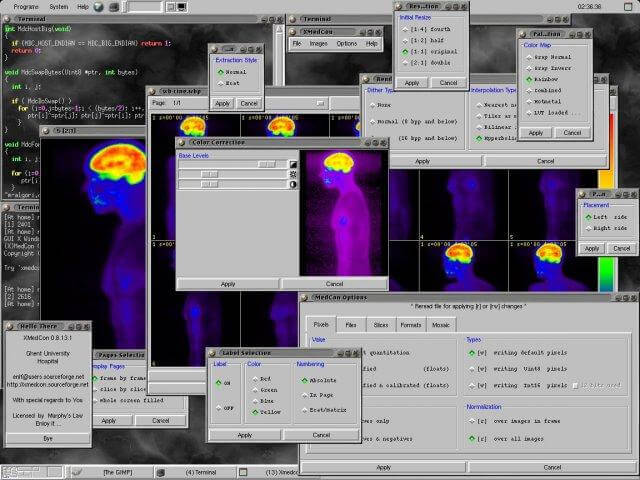

5. XMedcon

XMedcon is an open source medical image conversion toolkit and library developed mainly for converting reconstructed nuclear medical images.

You can use it to read unsupported files without compression, retrieve the raw binary/ASCII image arrays, to print pixel values, to write PNG for desktop applications, and to extract/reorder specified images among other functions.